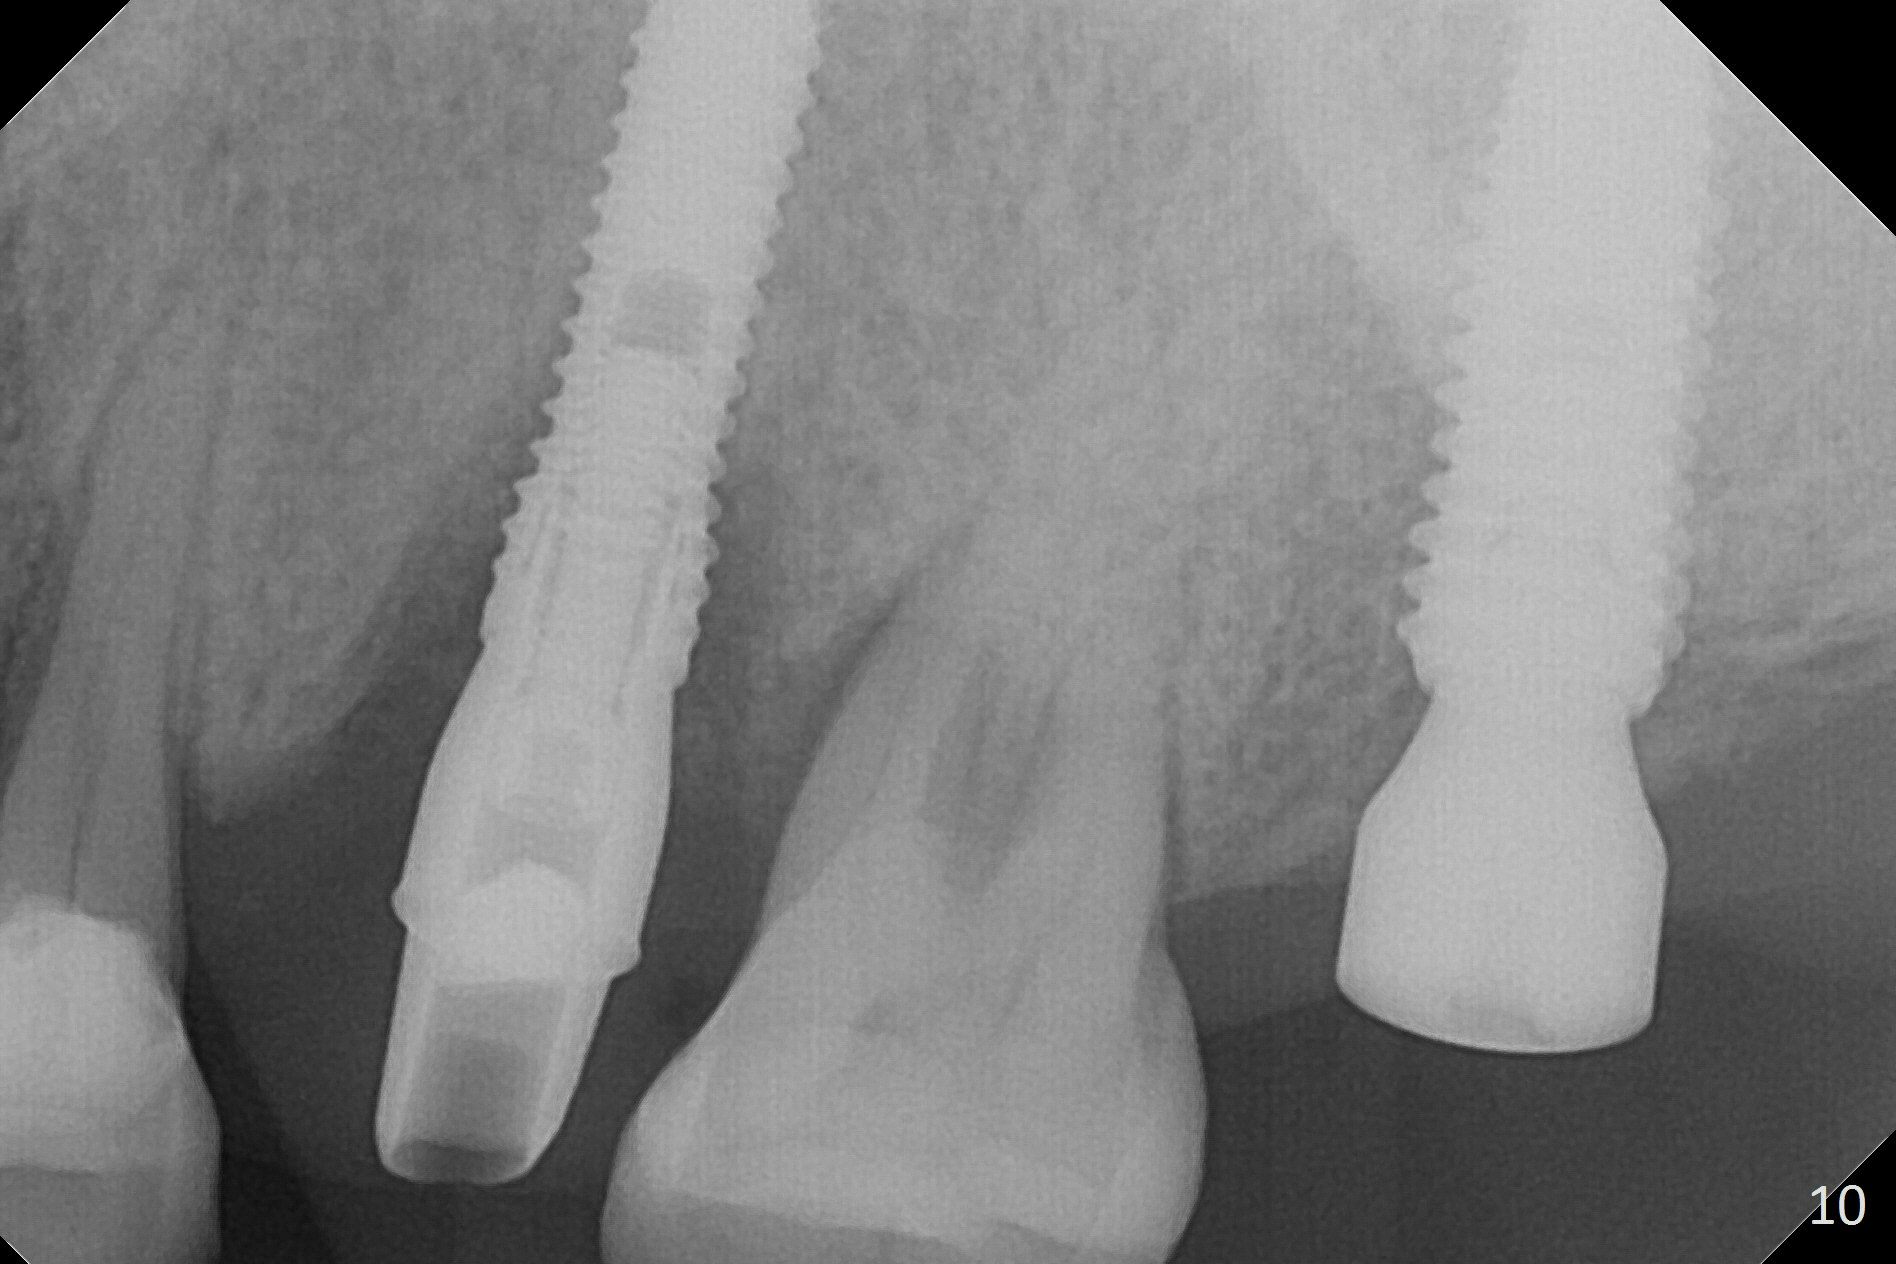

Initial osteotomy depth is 18 mm (Fig.1 green line) with 9 mm in the native bone (red line). The bone density feels to be low. There is at least 2 more mm bone apically (pink line). The depth is increased by 2 mm so that when a 3.8x15 mm implant is placed, there is 10-11 mm implant/bone contact (Fig.2 red line). There is large bony defect (Fig.3 *), which is bone grafted (Fig.4 *). Finally a longer abutment is placed (4.5x5.5(5) in Fig.4 vs. 4.5x4(5) in Fig.2,3). The 5 mm cuff does not look too long buccally (Fig.5) or palatally (Fig.6). To prevent postop buccal gingival overgrowth (2), the buccal margin of an immediate provisional is subgingival (Fig.7-9 *). Bone density between #13 and 14 appears to increase 3 months postop (Fig.10). The implant seems to be equi-crestal (Fig.11 ^). There seems to be more bone growth (i.e., decreasing gap) 6 months postop (Fig.12). Impression is taken. A crown is delivered nearly 7 months postop (08/07/2017). While there is minimal bone loss at #13 and 15 three years and 4 months post cementation, the tooth #14 and 18 are mobile (Fig.13,14).